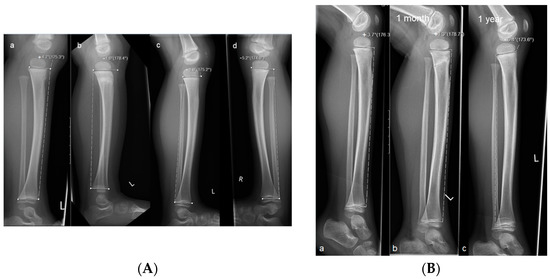

Figure 1. Measurements of the anterior tilt angle of the proximal tibia in children with trampoline fracture. (A) Radiographs of a child with a torus fracture. Measurements were taken (a) on the day of the accident; (b) after one month, and (c) after one year; (d) x-ray of the healthy opposite leg. The negative anterior tilt angle (−4.8°) at one year indicates complete remodeling. (B) Radiographs of a child with a complete fracture. Measurements were taken (a) on the day of the accident, (b) after one month, and (c) after one year. The negative anterior tilt angle at one year (−6.4°) shows complete remodeling.

The initial and follow-up radiographs were evaluated separately by two specialized pediatric radiologists. Fractures were classified as complete fractures or torus fractures. The anterior tilt angle of the tibia was measured according to our previous study [2] in a lateral radiograph of the lower leg. For this purpose, a tangent was drawn through the proximal and distal ends of the tibial epiphyseal plate. The proximal line of the angle was defined by drawing a tangent between the dorsal and middle points of the physis (the anterior point of the physis can be used if the line also intersects the middle point or two lines of the plate were visible, in which case the lower line was used for measurement). The distal part of the angle was determined by drawing a tangent between the dorsal and ventral epiphyseal plates of the distal physis (Figure 1). Strict or standardized lateral images are not necessary for the measurements of the anterior tilt angles. Measurements were performed with an angle measurement tool on a Sectra AB picture archiving and communication system (PACS IDS7TM, Version 19.3, Teknikringen 20, SE-58330 Linkoping, Sweden).